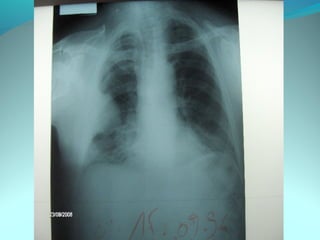

Opacité micronodulaire bilaterale diffuses et uniformement repartis

sur les 2 poumons realisant l’aspect d’une miliaire a petit grain

On note opacité latero trachiale ovalaire de 3cm de grand axe vertical

a limite ext des ADP médiastinale

Une opacité hilaire droite de 15 mm d’epaisseur

DIAGNOSTIC:

Miliaire tuberculeuse avec ADP mediastinal

Lymphome avec miliaire

Sarcoidose type2